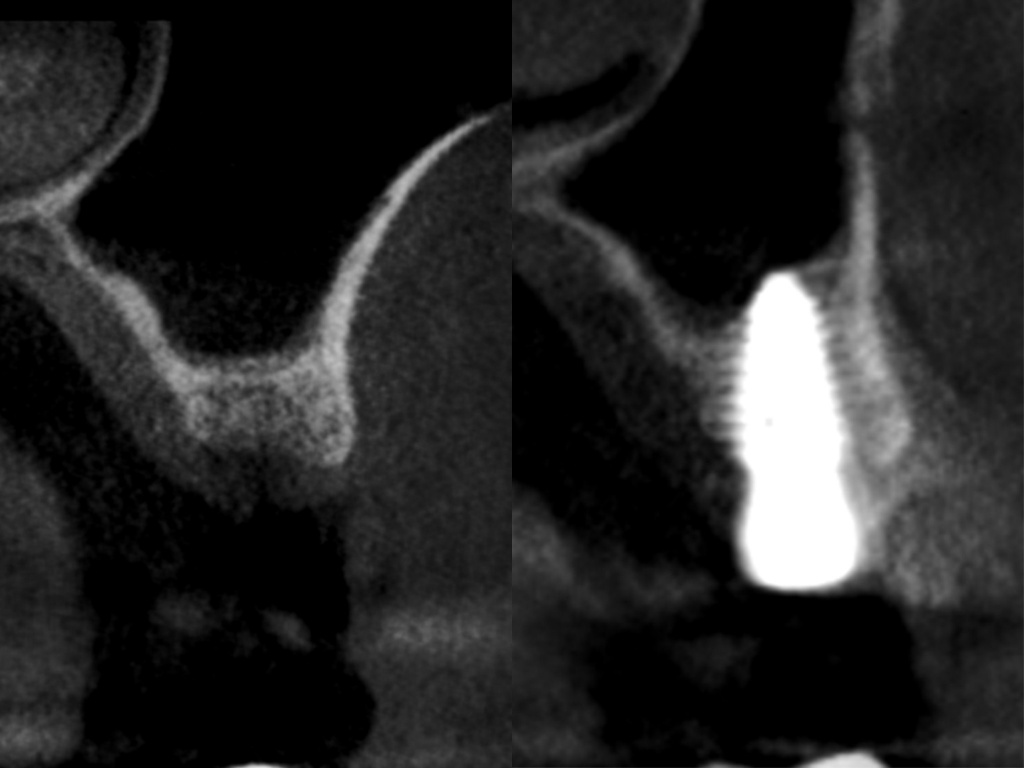

Имплантация AnyRidge с двусторонним закрытым синус-лифтингом.

Осложнения: правосторонний гайморит.